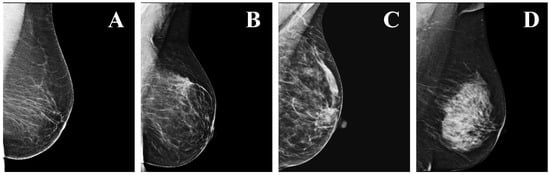

- Zheng, Y.; Yang, C.; Merkulov, A. Breast cancer screening using convolutional neural network and follow-up digital mammography. In Proceedings of the Computational Imaging III, International Society for Optics and Photonics, Orlando, FL, USA; 2018; Volume 10669, p. 1066905. [Google Scholar]

- Kooi, T.; Karssemeijer, N. Classifying symmetrical differences and temporal change for the detection of malignant masses in mammography using deep neural networks. J. Med. Imaging 2017, 4, 044501. [Google Scholar] [CrossRef] [PubMed]